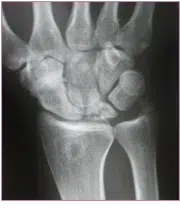

Der Gelenkverschleiß des Handgelenkes hat seine Ursache entweder in fehlverheilten Brüchen vor allem der Speiche oder des Kahnbeins, in Bandverletzungen der Handwurzel, einer rheumatischen Erkrankung oder Durchblutungsstörung einzelner Handwurzelknochen, die dann zum Absterben dieser führen kann. (z.B.: Morbus Kienböck).

Häufig sind zur langfristigen Schmerzverbesserung nur teilversteifende Operationen, oder aber die Entfernung einzelner Handwurzelknochen sinnvoll. Nach derartigen Operationen ist die Gesamtbeweglichkeit des Handgelenkes zwar reduziert – mit 30° Streckung und 30° Beugung- dies ist jedoch im Alltag meist ausreichend und das bei einer deutlichen Reduktion der vormalig vorhandenen Schmerzen.